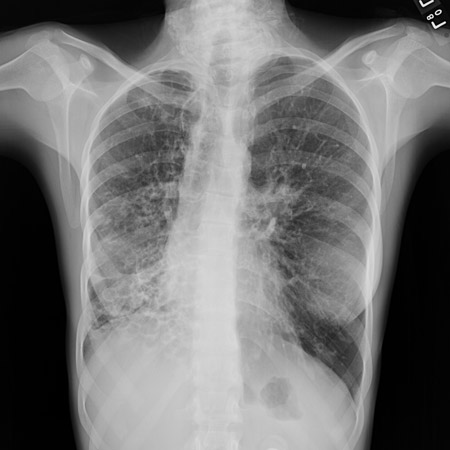

Chest x-ray showing increased opacification of the right perihilar region and superior segment of the right lower and upper lobes consistent with worsening aspiration pneumonia

From the personal collection of Dr R. Kanner, University of Utah School of Medicine